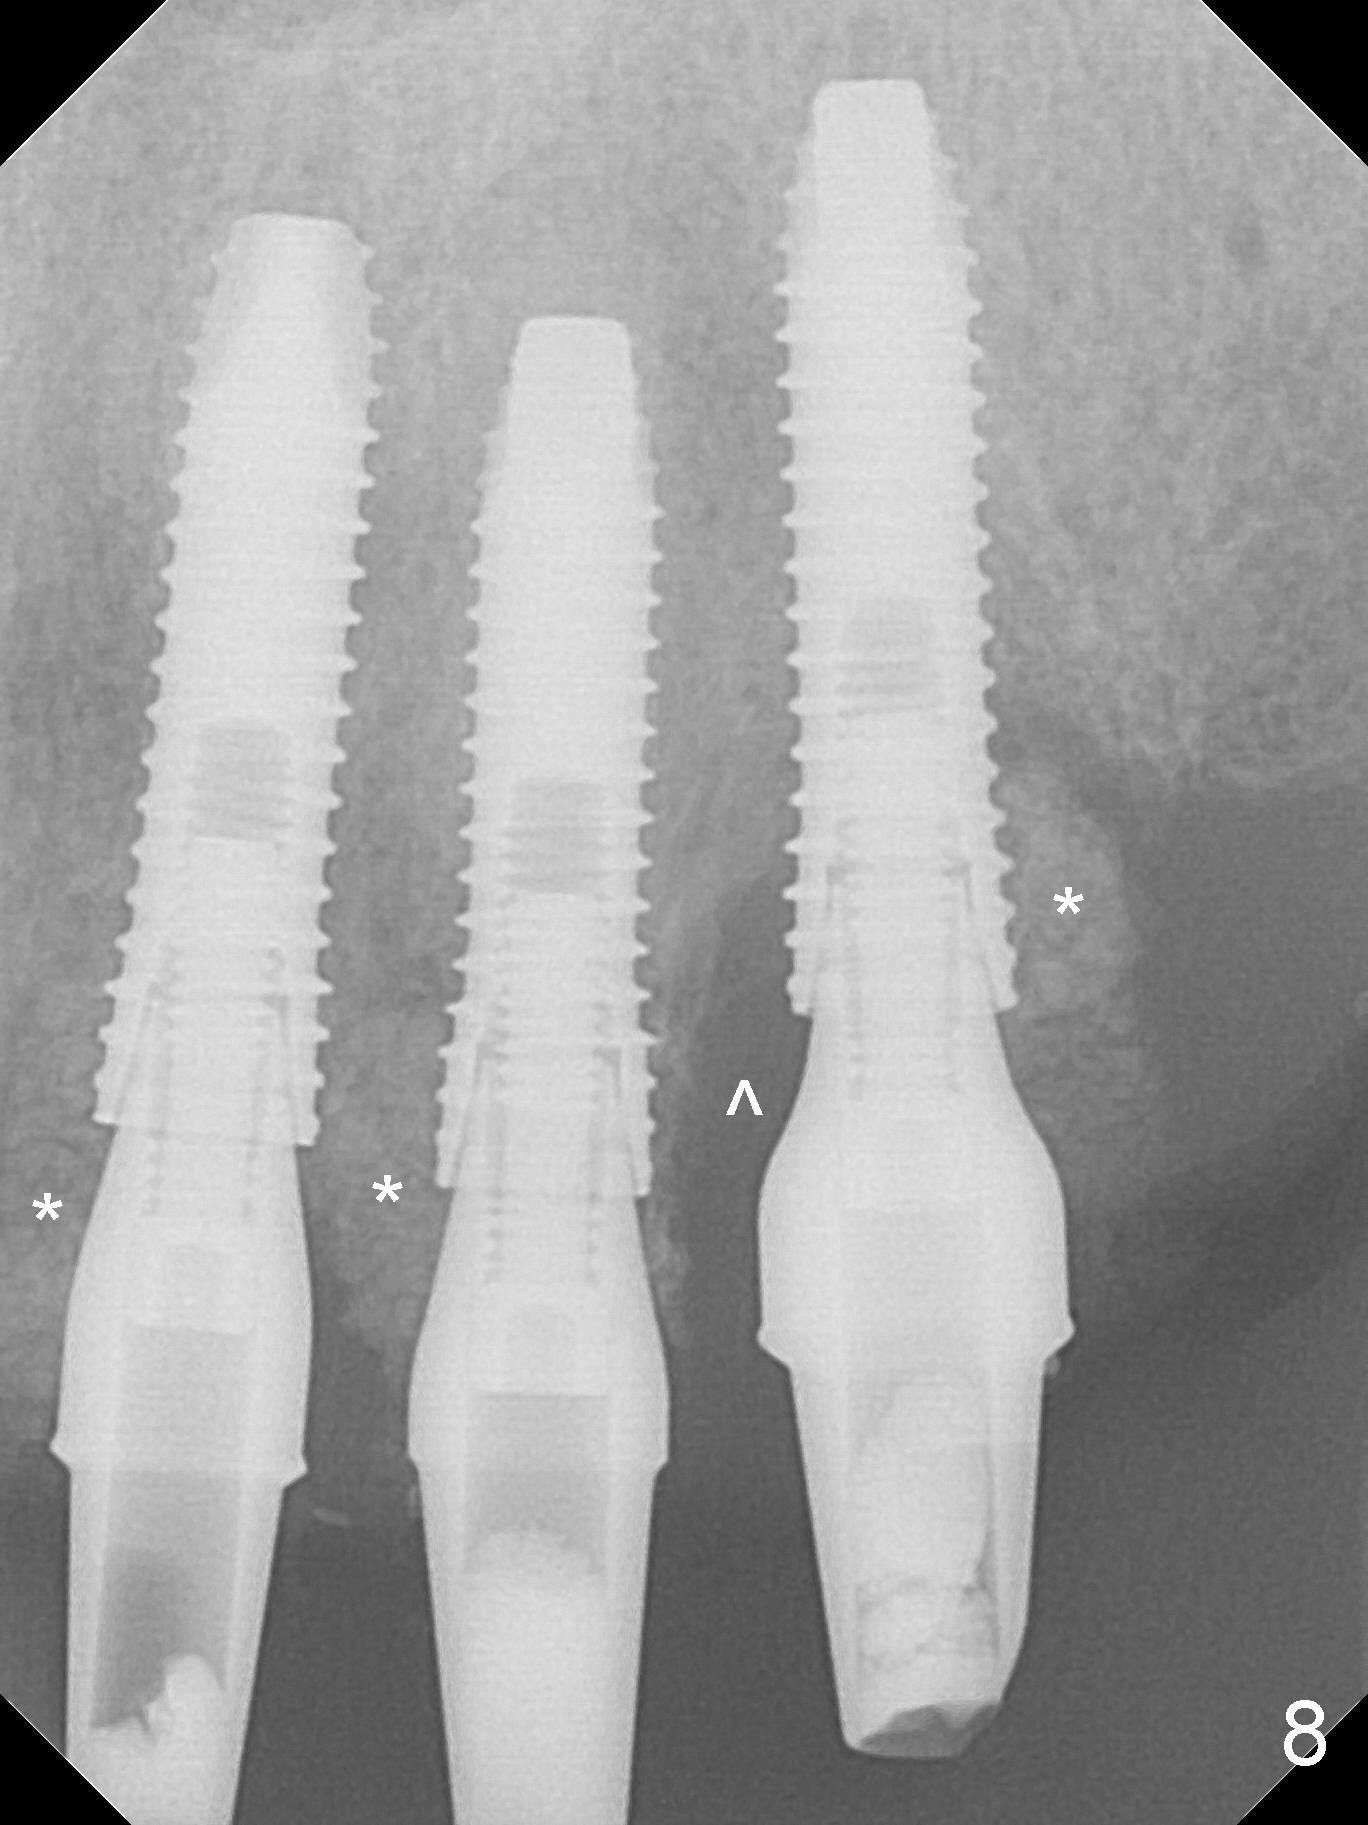

After use of 3 mm drill, the implant is reinserted at #11 with ideal trajectory (Fig.7). After further seating of the implant at #11, graft is placed in the remaining sockets of #9-11 (Fig.8 *; later more graft is placed mesial to #11 implant (^)). There appears no thread exposure 7 months postop (Fig.15,16).